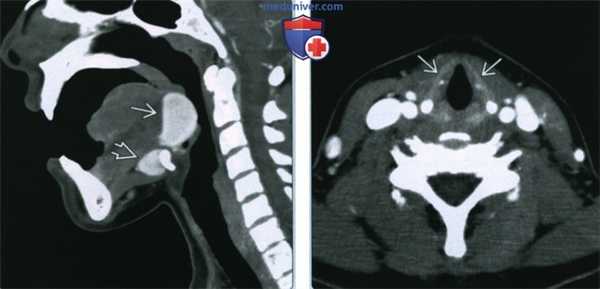

(Слева) На аксиальном рисунке изображена язычная щитовидная железа в задних отделах языка по средней линии, непосредственно глубже слепого отверстия. Четкие контуры и срединное расположение в области дна полости рта или в основании языка - типичные признаки язычной щитовидной железы.

(Справа) На аксиальной КТ с КУ в основании языка по средней линии определяется округлое контрастирующееся образование с четкими контурами, с минимальной деформацией подбородочно-язычных мышц. Плотность язычной щитовидной железы намного выше по сравнению с минимально контрастирующейся язычной миндалиной. (Слева) На аксиальной КТ с КУ в области дна по средней линии определяется объемное образование с четкими контурами, представленное эктопической тканью щитовидной железы неоднородной плотности (может быть сопоставимо с ранними изменениями при зобе).

(Справа) На аксиальной КТ с КУ в основании языка по средней линии определяется округлое контрастирующееся образование с четкими контурами, с минимальной деформацией подбородочно-язычных мышц. Плотность язычной щитовидной железы намного выше по сравнению с минимально контрастирующейся язычной миндалиной.